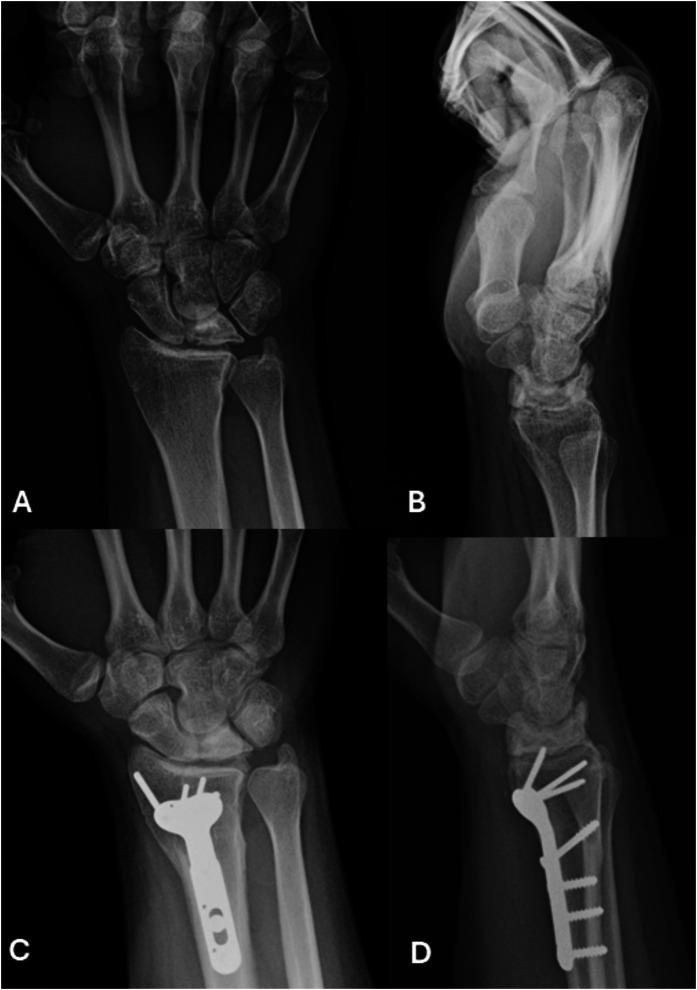

肯博克病:认识与治疗的最新进展

Kienböck Disease: Recent Advances in Understanding and Management.

➢ An at-risk lunate (due to anatomic factors) subjected to a trigger event (axial load, embolism, hypercoagulability) leads to the development of lunate osteonecrosis.➢ Children, adolescents, and elderly patients with Kienböck disease respond well to nonoperative treatments, and this should be considered before any surgical intervention.➢ For disease limited to the lunate, treatment decisions should be driven by the condition of the cartilage; intact lunate cartilage can be treated with joint leveling or core decompression, whereas disrupted cartilage surfaces should be bypassed with scaphocapitate or scaphotrapeziotrapezoid arthrodesis. Newer surgical procedures such as wrist arthroscopy and the introduction of contrast-enhanced magnetic resonance imaging have expanded the treatment options for these patients.➢ Once disease extends outside of the lunate, reconstruction with proximal row carpectomy or partial or total wrist arthrodesis should be considered on the basis of which articular surfaces are affected.➢ The new unified classification system and treatment are applicable to almost all patients with Kienböck disease.

摘要

➢ (由于解剖因素)处于风险中的月骨受到触发事件(轴向负荷、栓塞、高凝状态)影响会导致月骨缺血性坏死的发生。

➢ 患有月骨无菌性坏死的儿童、青少年和老年患者对非手术治疗反应良好,在进行任何手术干预之前都应考虑这一点。

➢ 对于局限于月骨的疾病,治疗决策应取决于软骨的状况;月骨软骨完整时可采用关节平整或髓芯减压治疗,而软骨表面受损时应采用舟头或舟大多角小多角关节融合术绕过。腕关节镜检查和引入对比增强磁共振成像等新的手术方法扩大了这些患者的治疗选择。

➢ 一旦疾病扩展至月骨以外,应根据受影响的关节面考虑采用近排腕骨切除术或部分或全腕关节融合术进行重建。

➢ 新的统一分类系统和治疗方法适用于几乎所有月骨无菌性坏死患者。